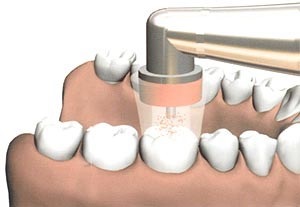

Ezüstözés tej fogak - ez egy eljárás szuvas régiók, amelyekben az ezüst bevonatot alkalmazunk. Ez az anyag baktériumölő és fertőtlenítő hatással alkalmazása után a fogakra alakított védőfóliát, amely megakadályozza a további fogszuvasodás kialakulásának és a fertőzés terjedése. Ilyen módszerrel meg lehet tartani a babát tejfog azok pótlásához az állandó. A külső foga nézetek előtt és után az eljárás megtalálható az alábbi fotó.

- alapos tisztítása a fogak plakk és az élelmiszer-részecskéket;

- alkalmazásával 30% ezüst-nitrát oldat egy sima felületre a zománc és a kezelés minden elváltozások egy vattacsomóval.